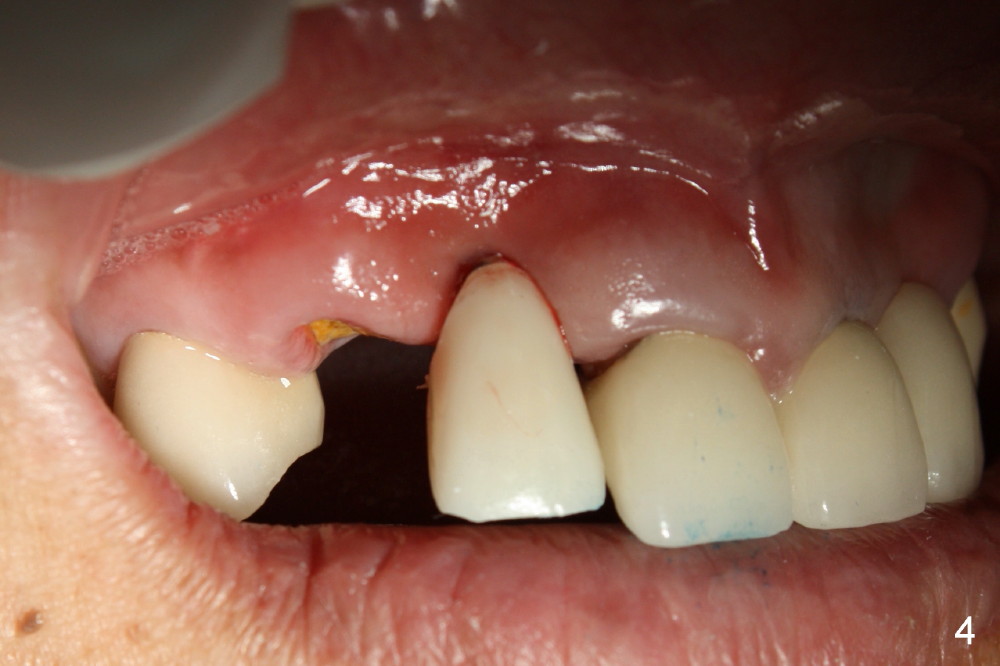

Finally the displaced implant is exfoliated itself, leaving a crater (Fig.1 arrowheads). CBCT shows the knife-edged ridge post exfoliation of the implant at the site of #7 (Fig.5, as compared to that prior to exfoliation). After using 1.5 mm pilot drill at 17 mm and 2.0 mm at 14 mm (Fig.5 insert), a 3.0x17 mm one piece angled (15 º) implant is placed (Fig.2, 10). Palatal view reveals that the implant is placed buccally (Fig.3); ideally the implant should be more palatal (Fig.3 insert: circle). Please take postop CBCT to confirm the placement. The buccal placement is partially related to the elongated tooth (Fig.4).